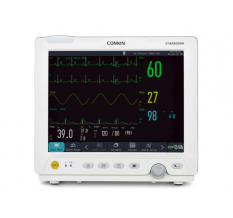

| Дисплей |

5", цветной, сенсорный |